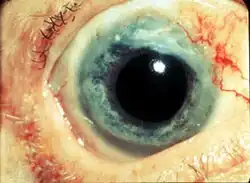

Granulomatosis with polyangiitis (GPA), formerly known as Wegener's granulomatosis (WG),[1][2][3][4][5] after German Nazi physician Friedrich Wegener, is a rare, long-term, systemic disorder that involves the formation of granulomas and inflammation of blood vessels (vasculitis). It is an autoimmune disease and a form of vasculitis that affects small- and medium-sized vessels in many organs, but most commonly affects the upper respiratory tract, lungs, and kidneys.[6] The signs and symptoms of GPA are highly varied and reflect which organs are supplied by the affected blood vessels. Typical signs and symptoms include nosebleeds, stuffy nose and crustiness of nasal secretions, and inflammation of the uveal layer of the eye.[3] Damage to the heart, lungs, and kidneys can be fatal.

Initial signs are highly variable, and diagnosis can be severely delayed due to the nonspecific nature of the symptoms. In general, irritation and nasal inflammation are the first signs in most people.[12][13] Involvement of the upper respiratory tract, such as the nose and sinuses, is seen in nearly all people with GPA.[14] Typical signs and symptoms of nose or sinus involvement include crusting around the nose, stuffiness, nosebleeds, runny nose, and "saddle-nose" deformity due to a hole in the septum of the nose.[7][14] Inflammation of the outer layers of the eye (scleritis and episcleritis[15][16]) and conjunctivitis are the most common signs of GPA in the eye; involvement of the eyes is common and occurs in slightly more than half of people with the disease.[6]